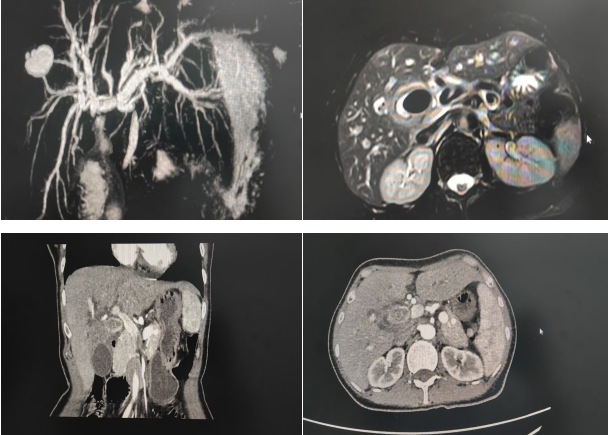

术前核磁及增强CT片

56岁女性患者,“梗阻性黄疸”收住普外科,患者入院后,经过腹部增强CT及MRCP检查显示:胆囊结石嵌顿伴胆囊炎,压迫邻近肝门部胆管致以上肝内外胆管扩张伴胆管炎,Mirizzi综合征需要手术治疗。普外科主任李琦带领团队充分讨论后,为患者制定了详细的手术方案。与患者及家属沟通并征得同意后,李琦主任带领手术团队密切合作,成功为患者实施了腹腔镜下胆囊切除+胆道修补成形+T管引流术,手术顺利。术后第二天,患者便能够下床活动,正常进食,术后第五天,复查肝功显示黄疸指数及转氨酶基本恢复正常。患者及家属非常满意。